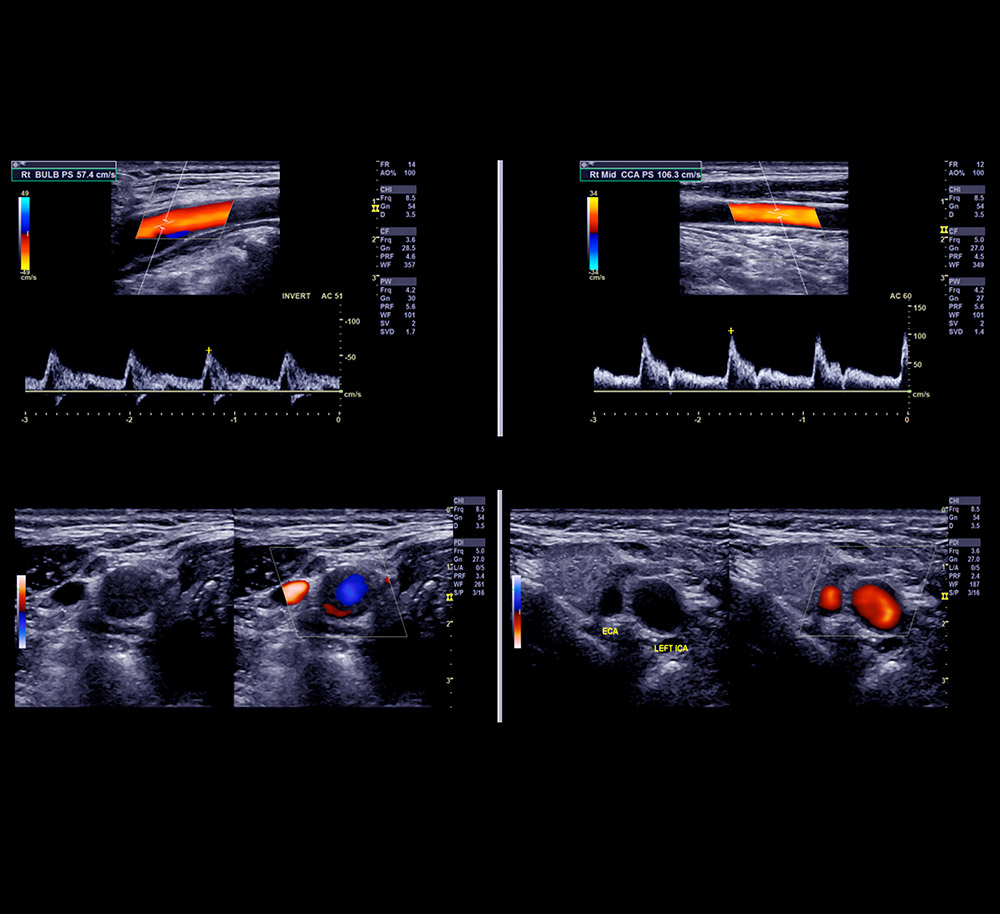

- Carotid Duplex